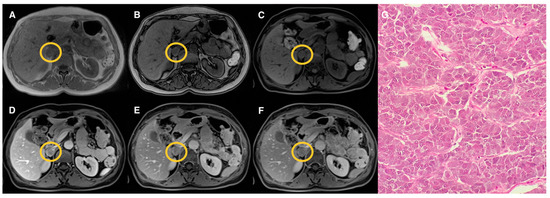

| Groups | Qualitative CS Signal Drop | Lesion Type | Total |

|---|---|---|---|

| 1 | Homogeneous | Adenomas (n = 19) | 19 |

| 2 | Heterogeneous | Adenomas (n = 17) Pheochromocytomas (n = 3) Myelolipomas (n = 3) | 23 |

| 3 | Absent | Adenomas (n = 10) Pheochromocytomas (n = 9) Primary malignant tumors (n = 5) Metastasis (n = 5) Oncocytoma (n = 1) | 30 |